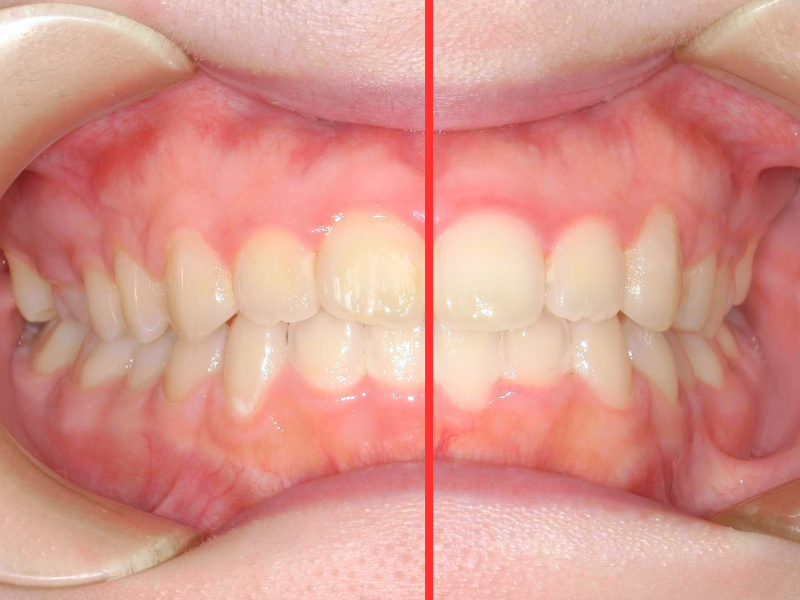

10代、女性、ワイヤー

| 施術内容 | 主訴:上下前歯でこぼこ。なるべく抜きたくない。 詳細:ワイヤー矯正での歯並び改善 詳細:ワイヤー矯正での歯並び改善 歯肉炎リスクあるため、今後は後戻りのチェックとともに歯肉炎管理もしていきます。 |

|---|---|

| 治療期間 | 12ヶ月(2/6現在 治療終了) |

| リスク・副作用 | ■リスク・副作用 ・治療の初期段階では、痛みや不快感が生じやすくなりますが、一週間前後で慣れます。 ・歯の動き方には個人差があるため、予想された治療期間より延長する場合があります。 |

| 費用 | ワイヤー矯正 60万円(税込660,000円) |